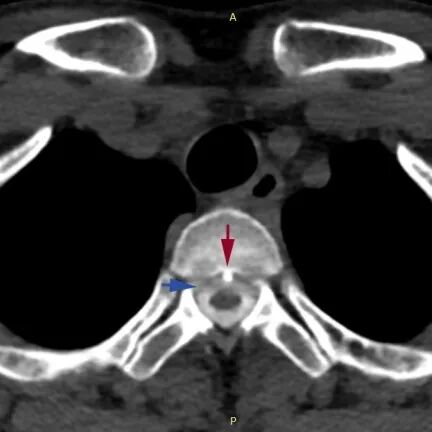

宋先生的脊柱磁共振检查 可见第2、3胸椎之间有“骨刺”形成(红箭头) 刺破硬脊髓膜,造成脑脊液外漏(蓝箭头) 案例二 无独有偶,今年25岁的江女士最近也因为类似问题住进了邵逸夫医院神经内科。 江女士是一位幼儿教师,上半年因为疫情影响需要给学生线上讲课,“原本颈椎就不好,线上课程需要重新备课,策划内容、准备PPT需要长时间电脑工作,花了很多时间准备,确实很疲劳”。 一周前,江女士开始感觉头晕、头重脚轻,逐渐变成直立性头痛(就是站着或坐着时,即刻出现头痛,全头发胀昏沉,后颈部和肩部发酸,平躺后即好转)。 到邵逸夫医院神经内科检查,很快明确诊断为颅内低压并伴有硬膜下出血。 检查显示,江女士的颈段椎间盘退变,形成骨刺并刺破了硬脊髓膜,造成了脊髓脑脊液渗漏,颅内压力过低还造成了脑膜血管撕裂和硬膜下出血。